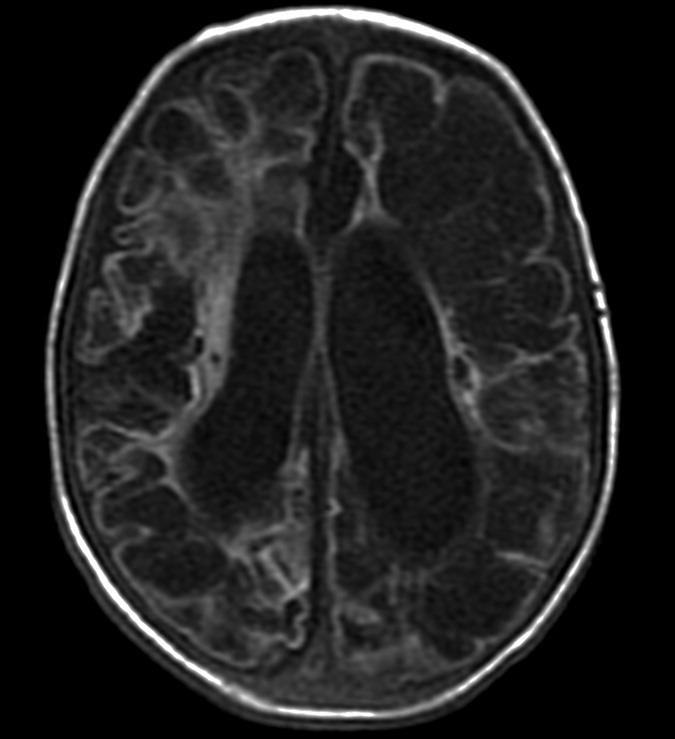

С рождения наблюдалась везикулезная сыпь в области лба. На аксиальной Т2-взвешенной томограмме определяется «missing cortex» симптом: потеря нормального изменения сигнала от коры (кора и белое вещество неразличимы) в обеих затылочных областях, больше слева.

Т1-взвешенная аксиальная томограмма: диффузная кистозная энцефаломаляция с компенсаторной вентрикуломегалией